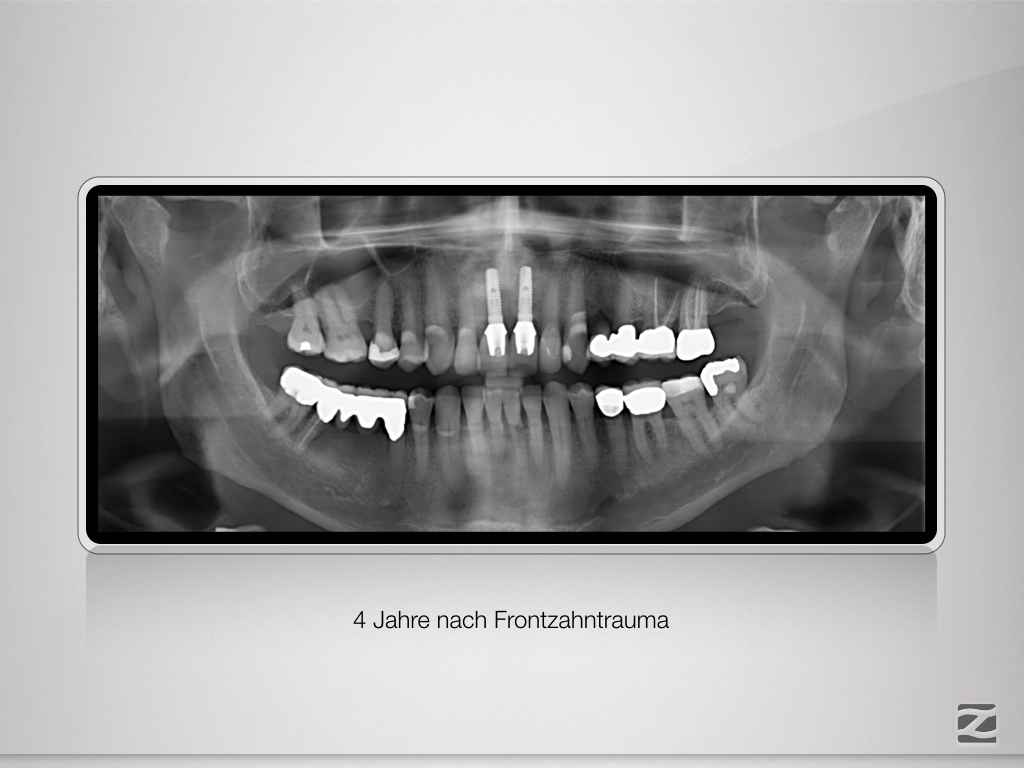

Trauma, externe Resorption & Pulpotomie